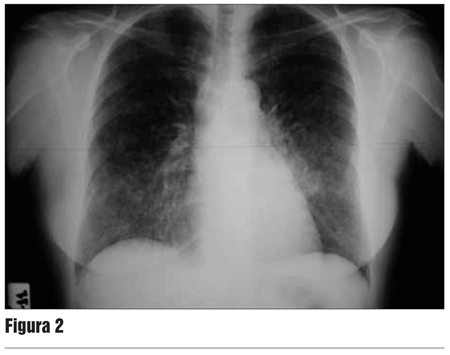

A los nueve meses es derivada al servicio de neumología por astenia, adinamia, sudoración profusa vespertina y fiebre de 39 ºC de temperatura axilar de 20 días de evolución. La evaluación diagnóstica mostró: viraje del PPD a 14 mm. Radiografía de tórax y tomografía computarizada de tórax de alta resolución (TC AR) con proceso intersticial micronodular difuso (figuras 2 y 3).